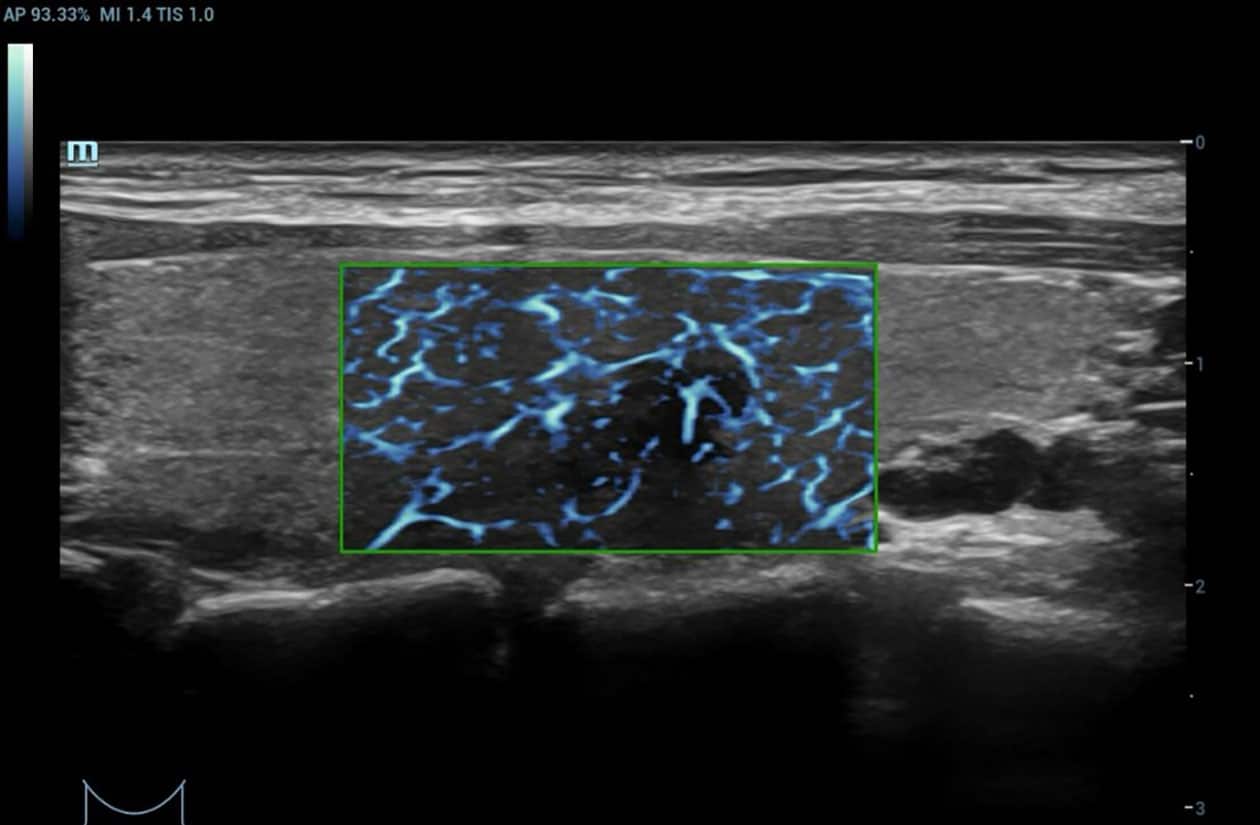

HD Scope

HD Scope is an advanced B-mode image processing technique that focuses additional imaging resources within a specified region of interest (ROI), analyzes the received channel data in unique ways, and applies various filtering and processing algorithms. This results in enhanced contrast resolution within the ROI based on the acoustic characteristics of varying tissue types.